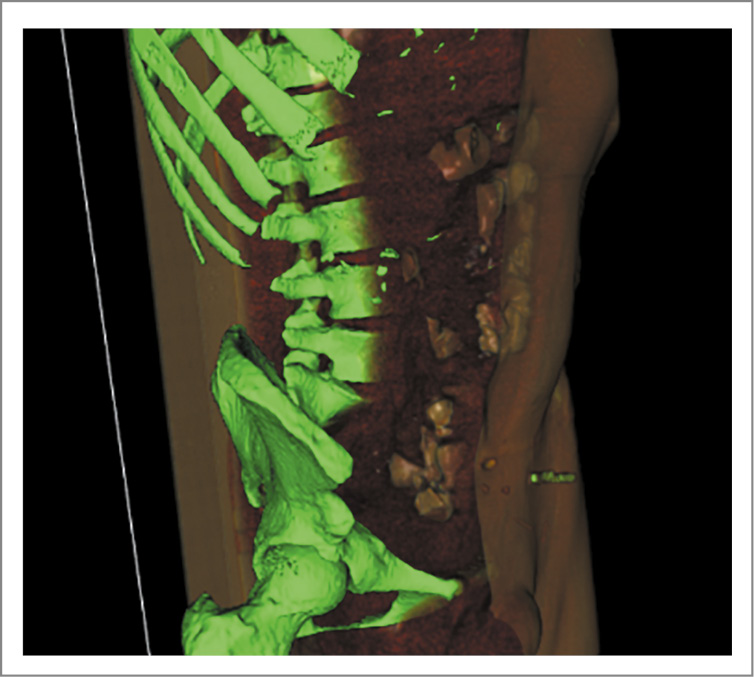

В клинике установлено, что длина дистальной части толстой кишки составляет 22 см, проксимальнее стомы сохранены поперечно-ободочная кишка и часть нисходящей ободочной кишки. Диастаз между участками кишки, пригодными для наложения анастомоза, составляет 10–11 см (рис. 1).

Рис. 1. Ирригоскопия.